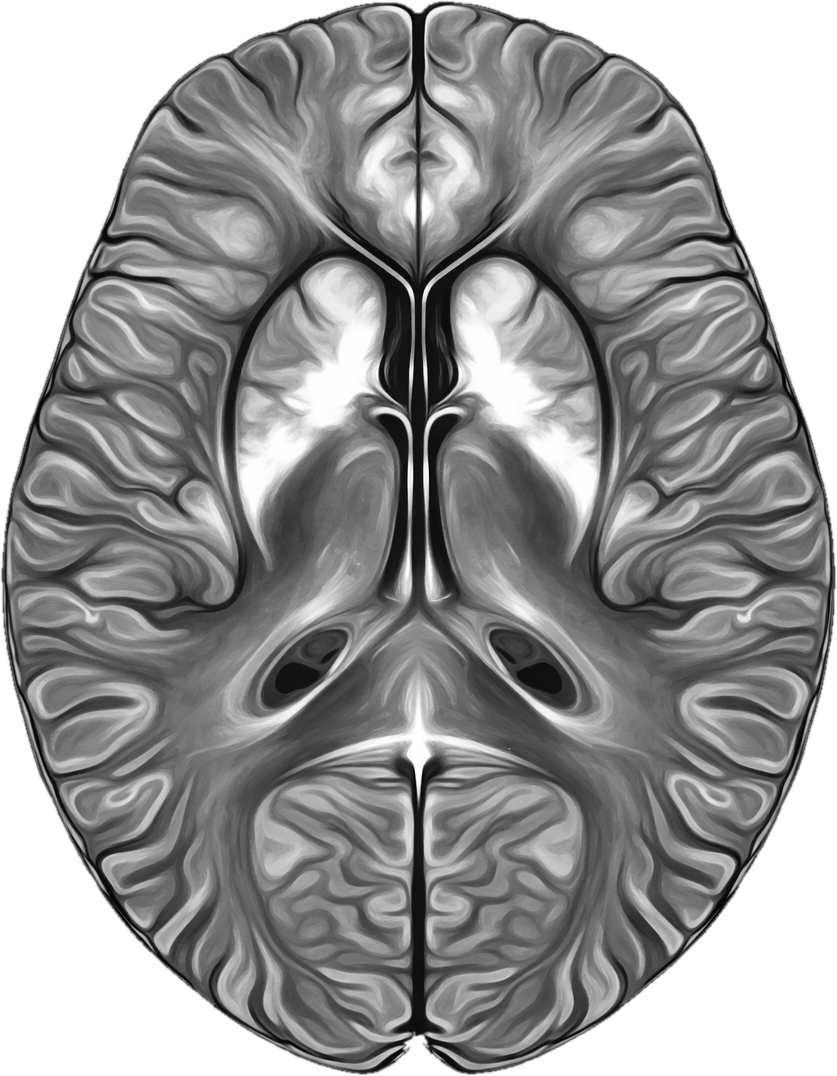

Quantitative Susceptibility Mapping in the browser

QSMbly is a browser-based application for Quantitative Susceptibility Mapping (QSM). It runs entirely in your web browser using WebAssembly, providing near-native performance without requiring any software installation or data upload.